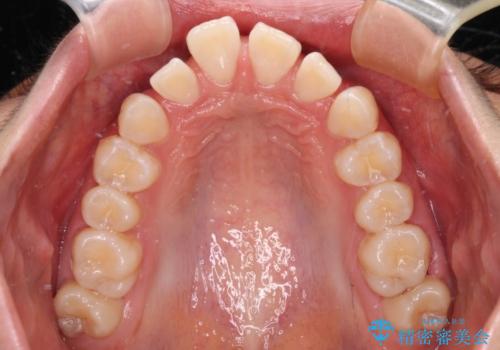

深い咬み合わせで前方に煽られた前歯 高校生のインビザライン矯正治療

- 前歯の隙間と前方に飛び出していることを気にして来院された患者様です。

咬み合わせも深くなっていたため、上顎臼歯を後方に移動させつつ、下顎の小臼歯を直立させ、奥歯の咬み合わせを改善する必要があります。

インビザライン単体で対応することも検討できますが、達成する可能性が低いため、カリエールディスタライザーという補助装置を併用して、より確実性を上げることとしました。

奥歯の咬み合わせと深い咬み合わせを改善した後、隙間などをインビザラインで整えることとしました。